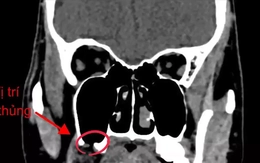

Nhổ 'răng khôn', người đàn ông bị đục thủng xoang hàm

Sống khỏe 2025-10-24T11:44:00Sau khi nhổ 'răng khôn' hàm trên tại một phòng khám tư, người đàn ông liên tục gặp hiện tượng lạ, mỗi khi uống nước, nước chảy ngược ra mũi. Sau nhiều tháng hứng chịu đau đầu, nghẹt mũi, ông đến bệnh viện kiểm tra thì được bác sĩ xác định bị thủng xoang hàm.